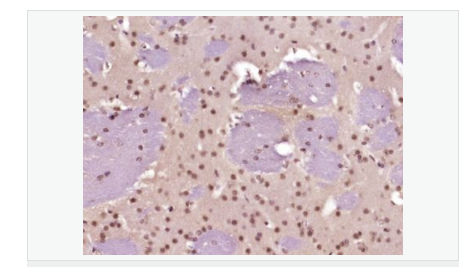

| 產(chǎn)品應(yīng)用 | WB=1:500-2000 ELISA=1:5000-10000 IHC-P=1:100-500 IHC-F=1:100-500 Flow-Cyt=1ug/Test ICC=1:100-500 IF=1:100-500 (石蠟切片需做抗原修復) not yet tested in other applications. optimal dilutions/concentrations should be determined by the end user. |

| 細胞定位 | 細胞核 |

| 產(chǎn)品介紹 | This gene encodes a member of the Notch family. Members of this Type 1 transmembrane protein family share structural characteristics including an extracellular domain consisting of multiple epidermal growth factor-like (EGF) repeats, and an intracellular domain consisting of multiple, different domain types. Notch family members play a role in a variety of developmental processes by controlling cell fate decisions. The Notch signaling network is an evolutionarily conserved intercellular signaling pathway which regulates interactions between physically adjacent cells. In Drosophilia, notch interaction with its cell-bound ligands (delta, serrate) establishes an intercellular signaling pathway that plays a key role in development. Homologues of the notch-ligands have also been identified in human, but precise interactions between these ligands and the human notch homologues remain to be determined. This protein is cleaved in the trans-Golgi network, and presented on the cell surface as a heterodimer. This protein functions as a receptor for membrane bound ligands, and may play multiple roles during development. [provided by RefSeq, Jul 2008]. Function: Notch family members play a role in a variety of developmental processes by controlling cell fate decisions. The Notch signaling network is an evolutionarily conserved intercellular signaling pathway which regulates interactions between physically adjacent cells. The protein is cleaved in the trans-Golgi network, and presented on the cell surface as a heterodimer. This protein functions as a receptor for membrane bound ligands. Once the Notch extracellular domain interacts with a ligand, a protease called TACE (Tumor Necrosis Factor Alpha Converting Enzyme) cleaves the Notch protein just outside the membrane. This releases the extracellular portion of Notch, which continues to interact with the ligand. The ligand plus the Notch extracellular domain is then endocytosed by the ligand expressing cell. After this first cleavage, an enzyme called gamma-secretase cleaves the remaining part of the Notch protein just inside the inner leaflet of the cell membrane. This releases the intracellular portion of the Notch protein, which then moves to the nucleus and causes various genes to be expressed. There are many other proteins involved in the intracellular portion of the Notch signalling cascade. Subunit: Heterodimer of a C-terminal fragment N(TM) and an N-terminal fragment N(EC) which are probably linked by disulfide bonds. Interacts with DNER, DTX1, DTX2 and RBPJ/RBPSUH. Also interacts with MAML1, MAML2 and MAML3 which act as transcriptional coactivators for NOTCH1. The activated membrane-bound form interacts with AAK1 which promotes NOTCH1 stabilization. Forms a trimeric complex with FBXW7 and SGK1. Interacts with HIF1AN. HIF1AN negatively regulates the function of notch intracellular domain (NICD), accelerating myogenic differentiation. Subcellular Location: Cell membrane; Single-pass type I membrane protein. Notch 1 intracellular domain: Nucleus. Note=Following proteolytical processing NICD is translocated to the nucleus. Tissue Specificity: In fetal tissues most abundant in spleen, brain stem and lung. Also present in most adult tissues where it is found mainly in lymphoid tissues. Post-translational modifications: Synthesized in the endoplasmic reticulum as an inactive form which is proteolytically cleaved by a furin-like convertase in the trans-Golgi network before it reaches the plasma membrane to yield an active, ligand-accessible form. Cleavage results in a C-terminal fragment N(TM) and a N-terminal fragment N(EC). Following ligand binding, it is cleaved by TNF-alpha converting enzyme (TACE) to yield a membrane-associated intermediate fragment called notch extracellular truncation (NEXT). Following endocytosis, this fragment is then cleaved by presenilin dependent gamma-secretase to release a notch-derived peptide containing the intracellular domain (NICD) from the membrane (By similarity). Phosphorylated (By similarity). O-glycosylated on the EGF-like domains. Contains both O-linked fucose and O-linked glucose. Ubiquitinated; undergoes 'Lys-29'-linked polyubiquitination catalyzed by ITCH. Monoubiquitination at Lys-1759 is required for activation by gamma-secretase cleavage, it promotes interaction with AAK1, which stabilizes it. Deubiquitination by EIF3F is necessary for nuclear import of activated Notch. Hydroxylated at Asn-1955 by HIF1AN. Hydroxylated at Asn-2022 by HIF1AN (By similarity). Hydroxylation reduces affinity for HI1AN and may thus indirectly modulate negative regulation of NICD. DISEASE: Defects in NOTCH1 are a cause of aortic valve disease 1 (AOVD1) [MIM:109730]. A common defect in the aortic valve in which two rather than three leaflets are present. It is often associated with aortic valve calcification and insufficiency. In extreme cases, the blood flow may be so restricted that the left ventricle fails to grow, resulting in hypoplastic left heart syndrome. Similarity: Belongs to the NOTCH family. Contains 5 ANK repeats. Contains 36 EGF-like domains. Contains 3 LNR (Lin/Notch) repeats. SWISS: P46531 Gene ID: 4851 Database links: Entrez Gene: 4851 Human Entrez Gene: 18128 Mouse Omim: 190198 Human SwissProt: P46531 Human SwissProt: Q01705 Mouse Unigene: 495473 Human nigene: 290610 Mouse Important Note: This product as supplied is intended for research use only, not for use in human, therapeutic or diagnostic applications. |